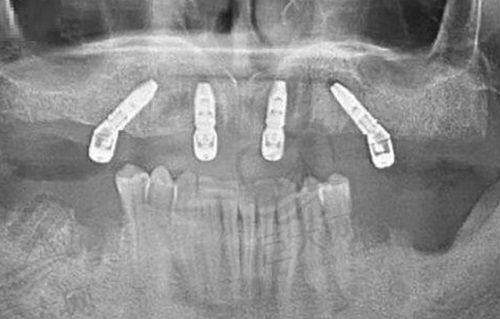

种植牙技术方面,即刻负重种植可以当天拔牙、当天种牙,大大缩短了治疗周期;All - on - 4/6技术半口仅需4 - 6颗植体,适合骨量不足的患者;亲骨种植针对骨质疏松人群,生物相容性更佳,能减少植骨需求。